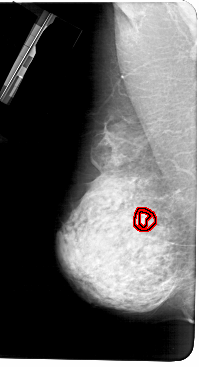

ics_version 1.0 filename A-1282-1 DATE_OF_STUDY 7 8 1995 PATIENT_AGE 54 FILM FILM_TYPE REGULAR DENSITY 4 DATE_DIGITIZED 7 7 1998 DIGITIZER HOWTEK 43.5 SEQUENCE LEFT_CC LINES 5266 PIXELS_PER_LINE 2761 BITS_PER_PIXEL 12 RESOLUTION 43.5 OVERLAY LEFT_MLO LINES 5491 PIXELS_PER_LINE 2971 BITS_PER_PIXEL 12 RESOLUTION 43.5 OVERLAY RIGHT_CC LINES 4951 PIXELS_PER_LINE 2461 BITS_PER_PIXEL 12 RESOLUTION 43.5 NON_OVERLAY RIGHT_MLO LINES 5446 PIXELS_PER_LINE 2776 BITS_PER_PIXEL 12 RESOLUTION 43.5 NON_OVERLAY |

FILE: A_1282_1.LEFT_MLO.OVERLAY TOTAL_ABNORMALITIES 1 ABNORMALITY 1 LESION_TYPE MASS SHAPE ARCHITECTURAL_DISTORTION MARGINS SPICULATED ASSESSMENT 4 SUBTLETY 1 PATHOLOGY BENIGN TOTAL_OUTLINES 2 BOUNDARY CORE |